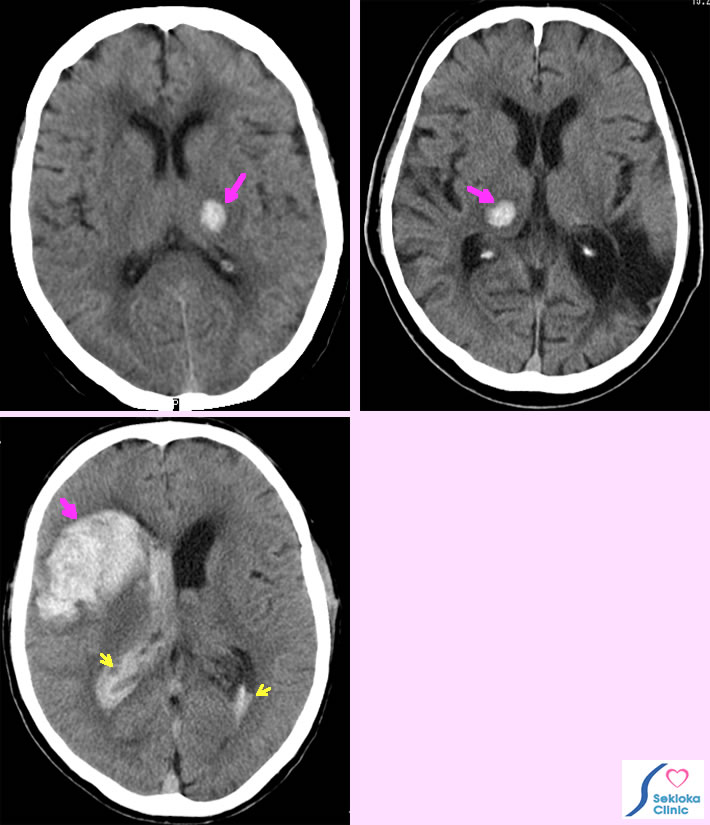

| 症状 | 症状は脳出血の部位で異なります。上段左の例は朝、右下肢がよろめいて来院され、検査。以前の血圧は160-170/90-100mmHgと高かったようです。上段右側の例はめまい感で来院され、 原因検査のためCT撮影。左側の大きな古い梗塞(黒い部分)に加え、新しい出血を認めます。下段の例は将棋をしていて突然倒れ、救急車で搬送されました。 |

| 診断 | CT(MDCT)。CTは出血の早期から診断でき、検査時間も短いため、交通事故などの全身打撲で全身を短時間で検索する場合にも高速撮影が可能なMDCTが使われます。下段の例は右前頭葉の大きな出血で脳室への血液流出(黄色矢印)も認めます。 |

| 治療 | 血腫による周囲の圧迫障害(循環障害)、脳ヘルニアを予防するため、浮腫を抑制する薬剤。大きい血腫では外科的除去。添付画像下段の例では緊急で右前頭部の血腫除去術が行われました。 上段の2例は安静観察で治療、その後リハビリ。 |